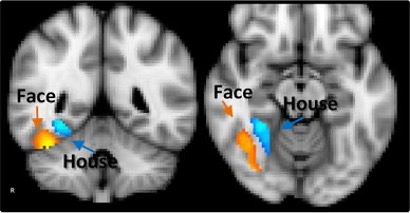

Where are the areas more active in Condition A than in Condition B?

How do pre-defined regions of interest respond in different experimental conditions?